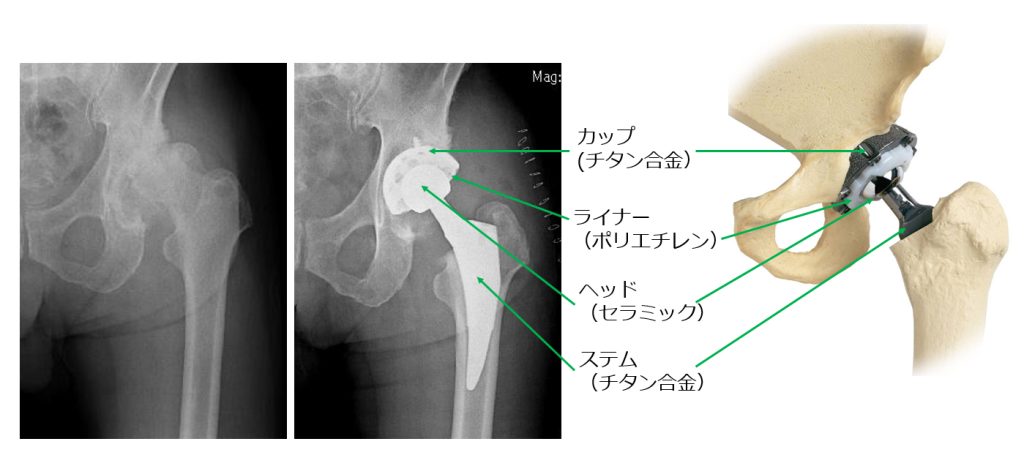

○人工股関節置換術

股関節の前方より約9cmの皮膚切開を加え、筋肉を切ることなく手術を行います。(最小侵襲手術:MIS)